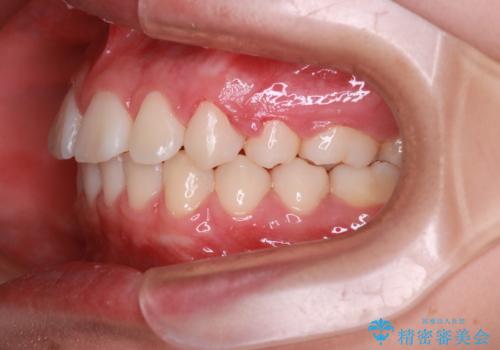

きれいな笑顔になったと喜んでいただけました。

上顎両側小臼歯を抜歯して治療を行い、突出感も大幅に改善しました。